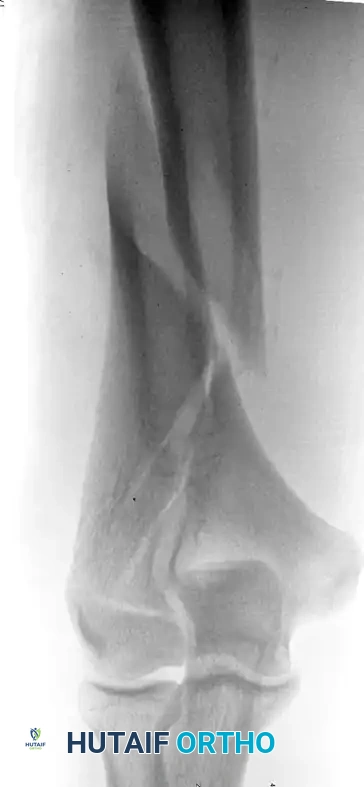

Distal humeral fracture

Preoperative AP radiograph of a distal humeral fracture with severe intraarticular extension.

Direct medial lateral plate

Postoperative radiograph demonstrating anatomic reduction after direct medial and lateral parallel plate fixation.